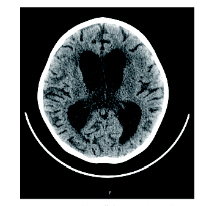

周正根(影像科主治医师):根据患儿的影像学图片介绍一下TBM的影像学特点, 首先, TBM比较容易出现脑积水, 见图1, 在脑底部的脑池可见分泌物, 脑室壁增厚; 其次, 脑室、脑沟可见到钙化, 见图2和图3, 钙化灶对结核的诊断有一定意义; 第三, 由于TBM可能侵犯到小血管, 所以可以见到一些低密度的梗塞病灶。

影像学检查(头颅CT平扫及胸部增强CT)示:(1)考虑交通性脑积水, 请结合临床。(2)考虑右中下肺感染并少量胸腔积液, 建议治疗后复查。(3)纵隔及右肺门淋巴结肿大, 反应性增生所致可能性较大。